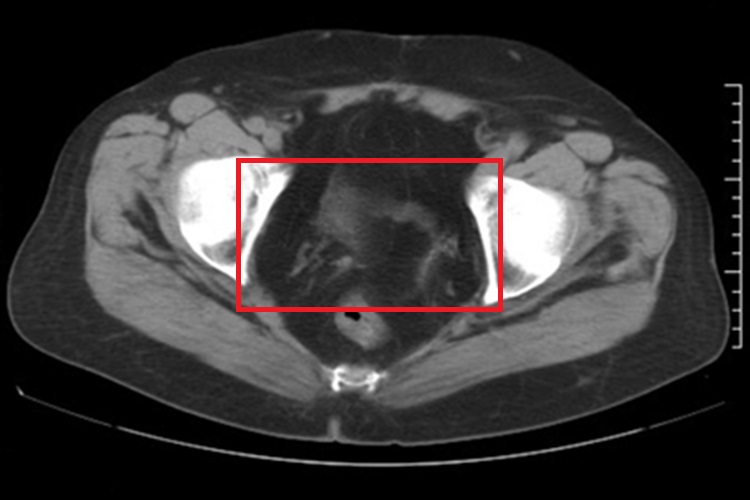

子宫切除后恢复以后,腹腔镜手术患者腹部可见有较浅的瘢痕形成。另外,患者影像学检查可见子宫体、子宫颈缺如。

子宫切除术可经腹腔镜或经阴道等途径进行,而腹腔镜手术时腹部会有3-4个穿刺点,分别位于肚脐处,左、右侧腹部,耻骨联合上方。腹腔镜伤口较小,伤口恢复后局部遗留淡红色瘢痕,无明显增生。影像学检查可见子宫体、子宫颈缺如,阴道残端可出现条带状软组织密度影。